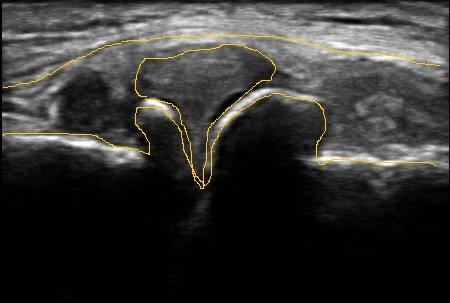

変形性膝関節症の内側の関節です。高齢者で膝が痛い、O脚で曲がっている、膝に水がたまりやすい方、階段がつらい方、正座ができないなど、、関節が太くなって変形しています。膝の軟骨が減って半月板が外に飛び出している画像です。